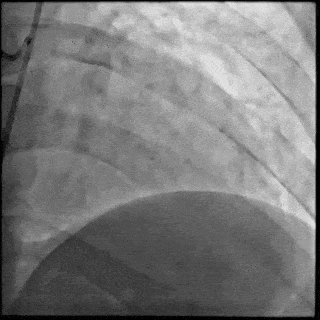

【DSA图 左冠治疗前造影】

5月28日8:00,葛均波院士团队在中山医院16号楼16楼中伟厅成功连线喀什二院导管室,沪喀远程手术正式开始。8:35,新疆喀什二院导管室内股动脉入路通路建立后,行左右冠脉造影示左前降支中段存在85%的严重狭窄,狭窄位于血管分叉路口且紧邻心肌桥;且左回旋支中段近乎闭塞,血管细窄且迂曲,病变弥漫。8:59,葛院士于上海操控血管介入机器人主端PANVIS COF,将指引导管送至左冠脉开口,并操控主支导丝和分支血管保护导丝通过狭窄病变,后送至前降支和对角支血管远端以建立轨道,同时利用介入机器人的微速调整功能避开心肌桥,以亚毫米级精准定位释放1枚支架。在成功处理患者左前降支病变后,葛院士通过搓捻机械操纵杆,远程精细调整导丝“进攻”方向,顺利通过左回旋支次全闭塞病变。因血管相对细小且病变弥漫,葛院士决定采用单纯球囊扩张术处理,即刻造影提示几乎无残余狭窄,避免了额外的支架植入。10:10,撤出所有导丝及导管,手术顺利结束。